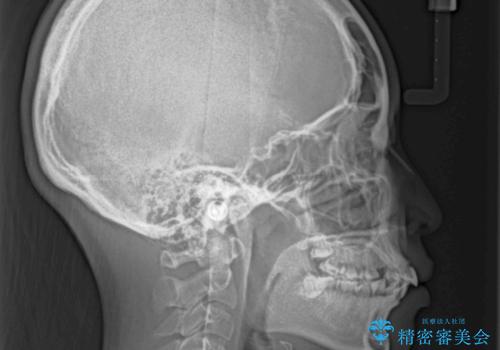

- 口元の閉じにくさを気にして来院された患者様です。

地元で矯正治療を始める予定で上顎左右第1小臼歯2本を抜歯したものの、その後転居したため治療が滞っているとのことでした。

上下ともに歯列が前方に突出していたため、上下左右の第一小臼歯4本を抜去する方針(既に上顎は抜歯されています)で、ワイヤー装置による矯正治療を行うこととしました。